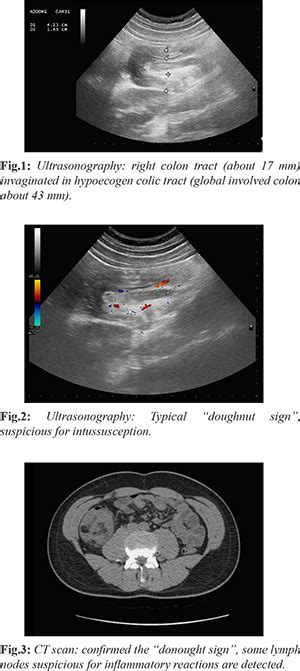

Large-B-Cell Lymphoma causing Intussusception in a Young Male: A ...